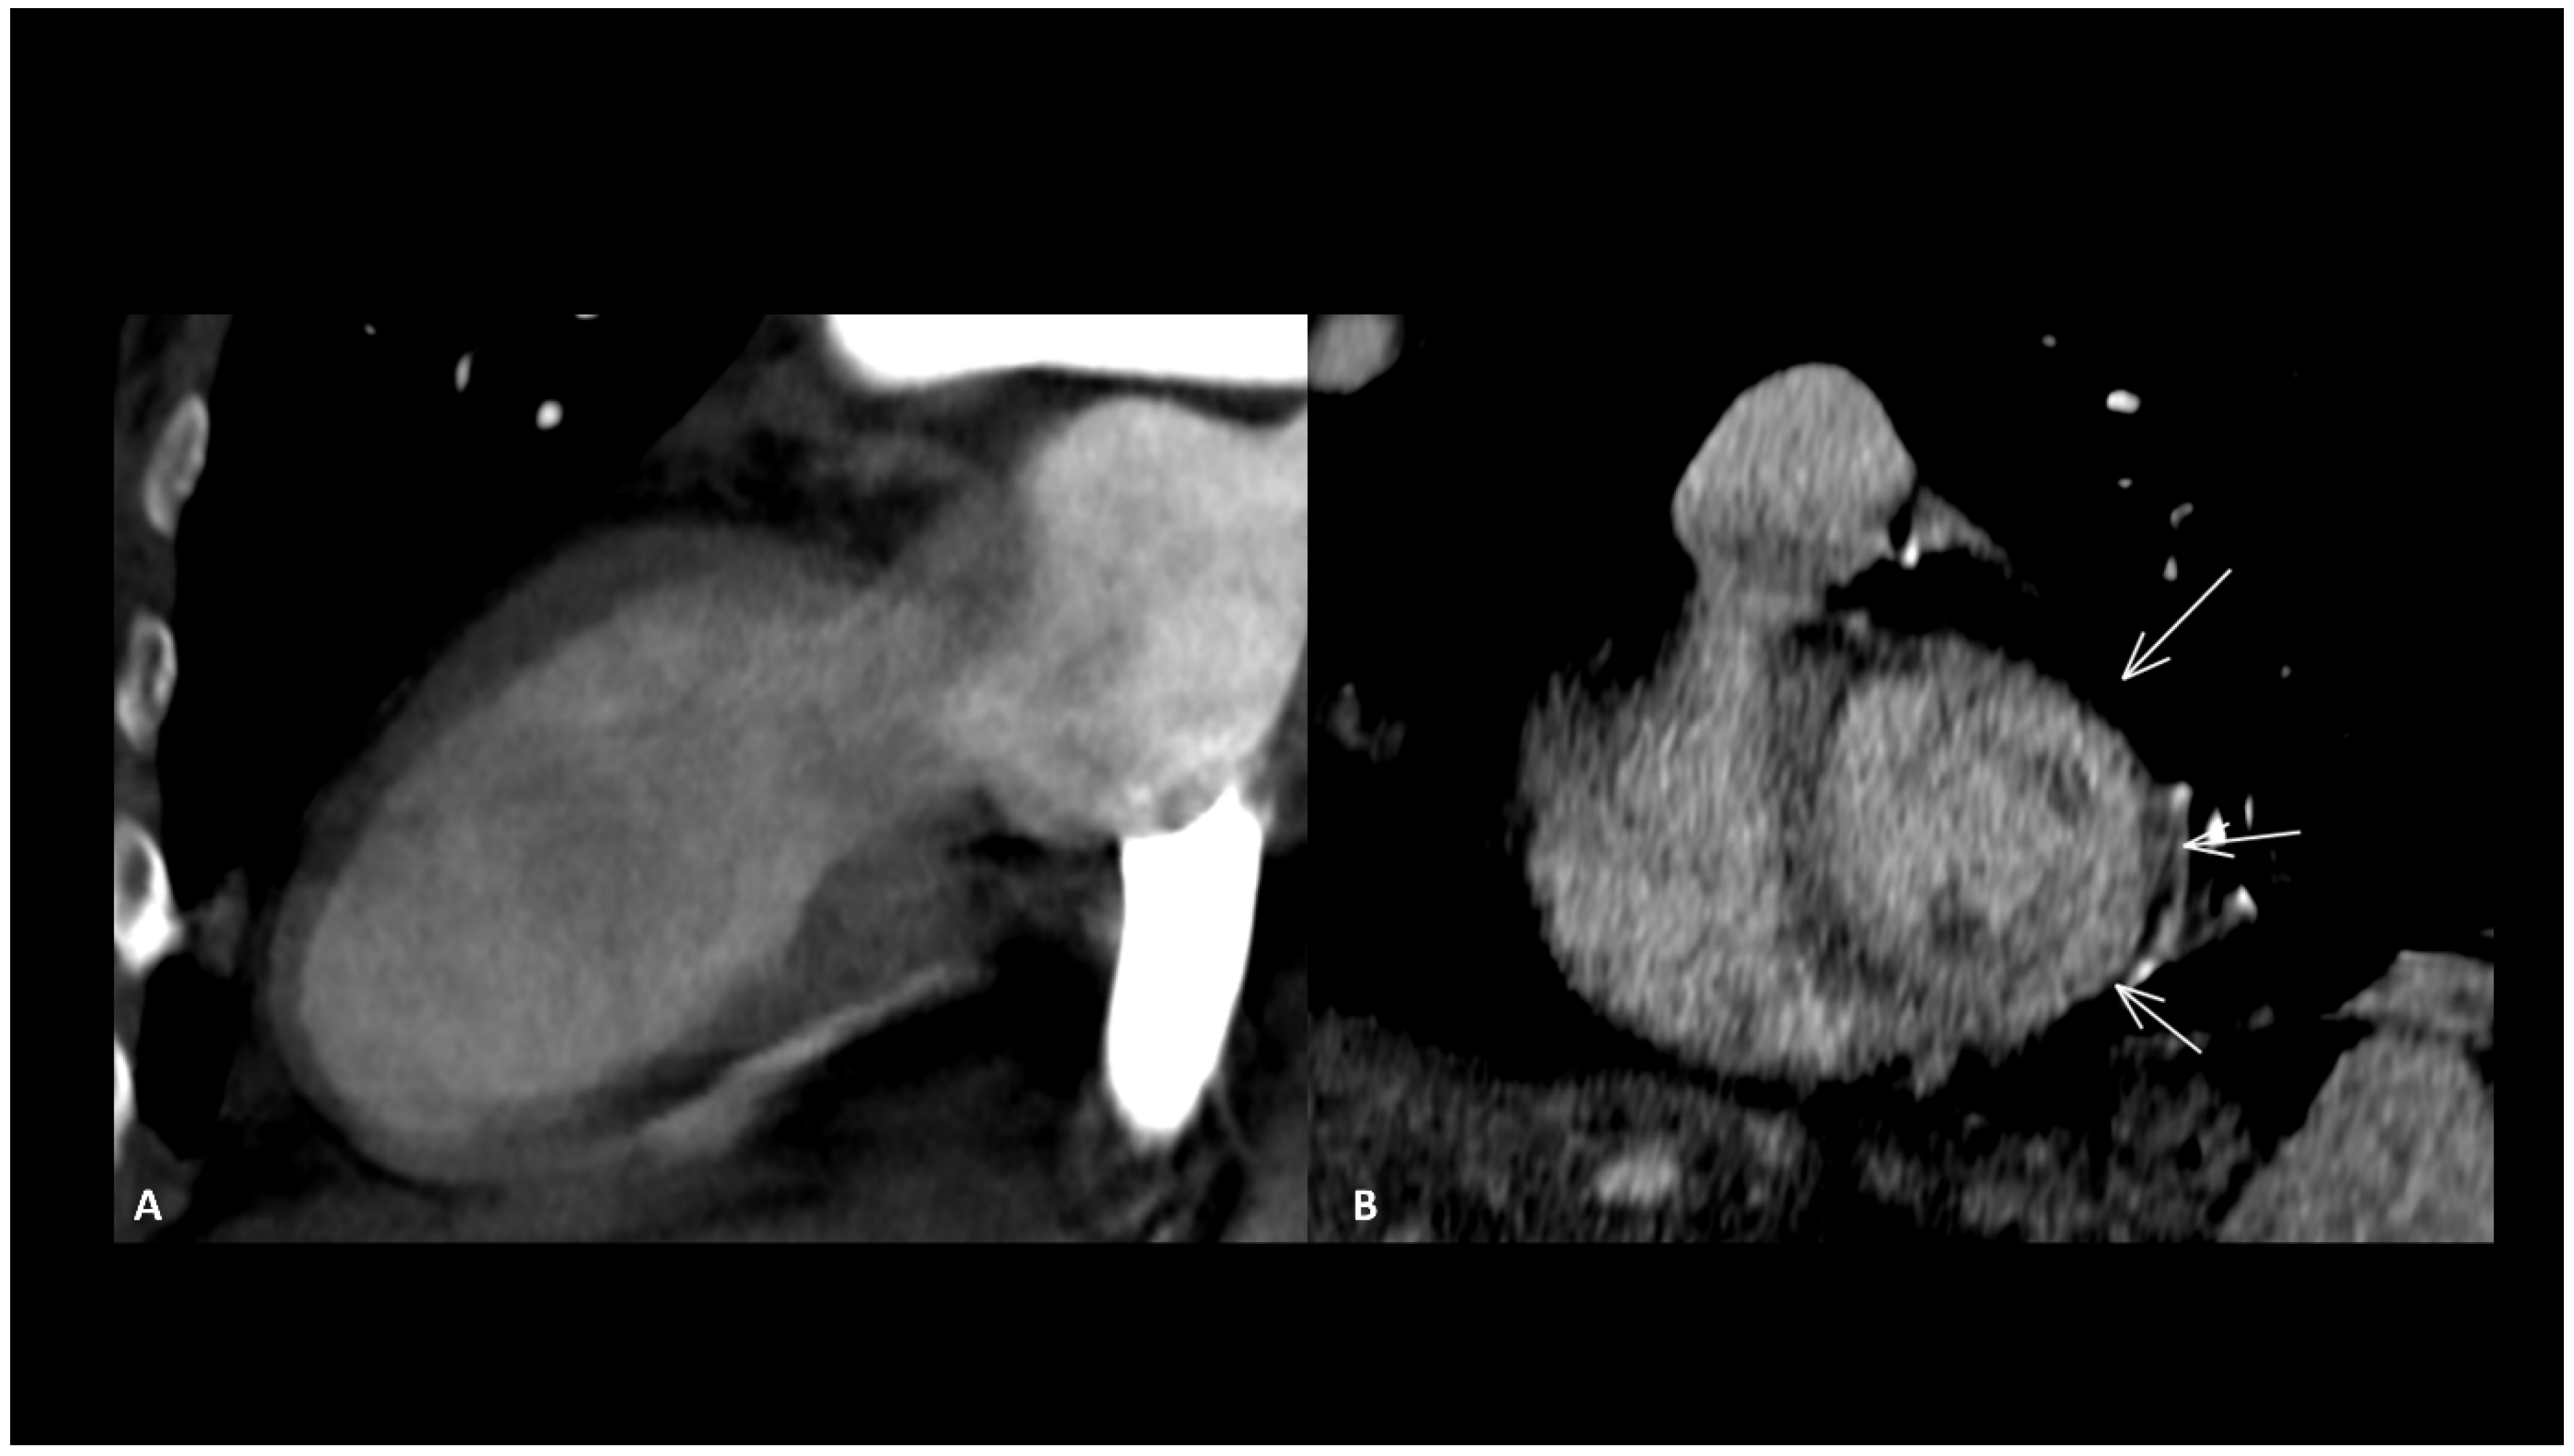

Other reported cardiac toxicities include non-inflammatory cardiomyopathy with impaired function, arrhythmias, and Takotsubo syndrome, either occurring independently or as a consequence of myocarditis [24,69]. These cardiac manifestations associated with ICIs typically carry a worse prognosis compared to those arising from other causes [70]. Takotsubo disease is characterized by an acute but reversible left ventricular systolic impairment with severe heart failure caused by physical or emotional stress, which typically recovers in a few days or weeks. It generally affects the apical wall in 80% of cases [71]. This localized impairment produces a typically regional ventricular dilatation sparing the basal segment, called “ballooning” which can be seen in the end-diastole (Figure 5). CMR is the modality of choice to assess function, the ballooning feature as well as T2 myocardial edema [71]. Rare cases of coronary spasm after ICI administration which promptly resolved with nitroglycerin have been reported [65]. In the absence of pre-existing coronary heart disease, the pathogenetic mechanism suspected is a T-cell-mediated vasculitis.

Figure 5.

Immune-related Takotsubo disease in a patient treated with anti-PD-1 for recurrent cervical cancer. The patient presented sudden functional impairment with extended akinesia of the mid-cavity and apical wall, with a drop of up to 35% of the ejection fraction. A CT acquired for pulmonary embolism shows apical and mid-cavity ballooning of the left ventricle (A) in the two-chamber view and extended myocardial enhancement of the mid-wall (arrows) (B). Due to the severe clinical compromise, cardiac magnetic resonance was not performed. The diagnosis was obtained after complete recovery of the ventricle function a few days later.